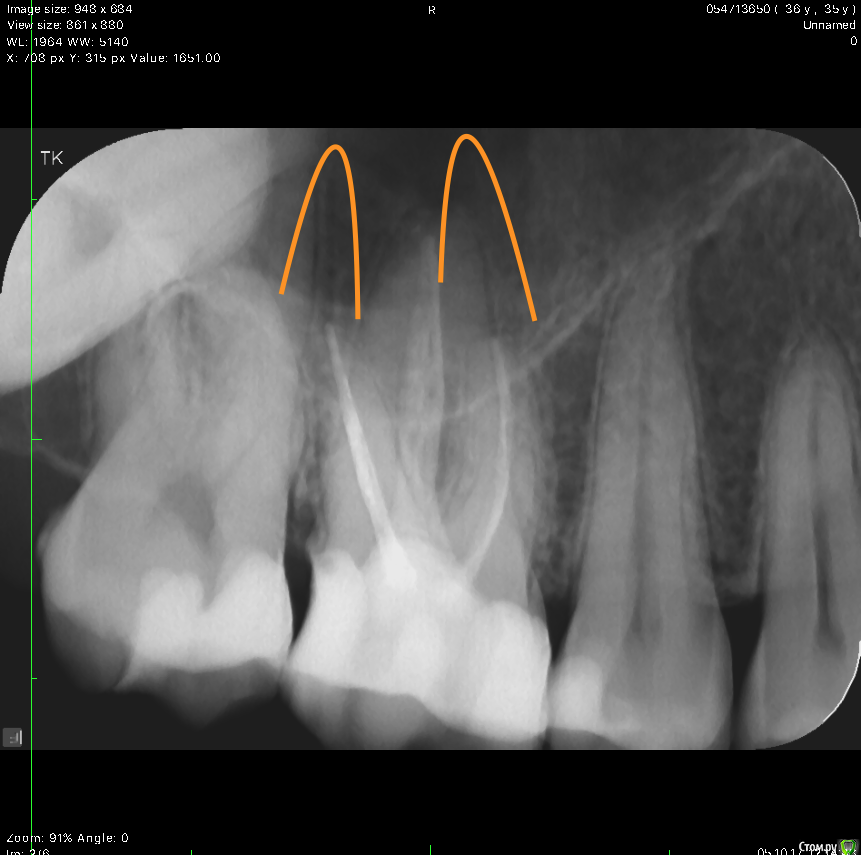

krokomot Опубликовано 5 октября, 2017 Поделиться Опубликовано 5 октября, 2017 http://http://s019.radikal.ru/i639/1710/da/f5e5ba37932d.pngканалы запломбированы до верхушек в 6-ом зубе, но вопросы к 7-ому 2 Ссылка на комментарий

Руслан81 Опубликовано 5 октября, 2017 Автор Поделиться Опубликовано 5 октября, 2017 каналы запломбированы до верхушек в 6-ом зубе, но вопросы к 7-ому а что с 7-м? Ссылка на комментарий

shishok Опубликовано 5 октября, 2017 Поделиться Опубликовано 5 октября, 2017 а что с 7-м? Близкое расположение пульпы к дну кариозной полости. 1 Ссылка на комментарий

DmitrySH Опубликовано 5 октября, 2017 Поделиться Опубликовано 5 октября, 2017 на снимке в посте №6 видна кариозная полость на передней поверхности зуба 37, на последнем снимке хуже видно Ссылка на комментарий

Руслан81 Опубликовано 6 октября, 2017 Автор Поделиться Опубликовано 6 октября, 2017 на снимке в посте №6 видна кариозная полость на передней поверхности зуба 37, на последнем снимке хуже видноэто не кариес, снимок просто такой Ссылка на комментарий

DmitrySH Опубликовано 6 октября, 2017 Поделиться Опубликовано 6 октября, 2017 это не кариес, снимок просто такой блаженны верующие Ссылка на комментарий

Руслан81 Опубликовано 7 октября, 2017 Автор Поделиться Опубликовано 7 октября, 2017 блаженны верующие Ну я думаю немецкий специалист, как и московский (ваш коллега) который до него смотрел снимки увидели бы "такой" обширный кариес. Ссылка на комментарий